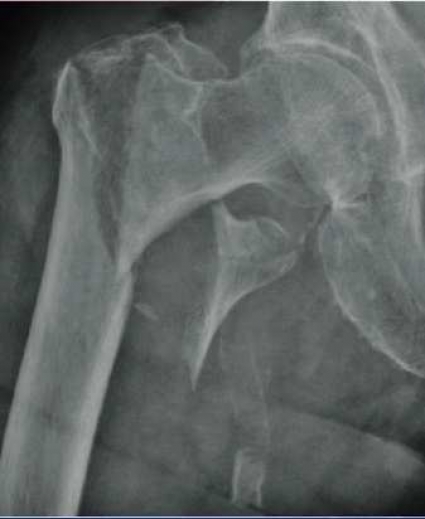

Årlig infusion ger färre nya frakturer och minskad dödlighet vid höftfraktur

Frakturer hos äldre är ett ökande folkhälsoproblem med stora sjukvårdsekonomiska konsekvenser. Med ökande ålder ökar både osteoporos och fallbenägenhet. Höftfraktur är en av de allvarligaste effekterna av osteoporos. Samtliga patienter erfordrar operation och sjukhusvård. Andra befintliga sjukdomar försvårar rehabiliteringen. Vid 50 års ålder är risken framöver att få en höftfraktur 23 procent för kvinnor och 11 procent för män [Läkartidningen. 2006;103: 2990-2.]. Kostnaden första året efter en höftfraktur har beräknats till 130 000 kronor, och den totala årliga kostnaden i Sverige för samtliga osteoporosrelaterade frakturer har beräknats till 4,6 miljarder kronor [Osteoporos Int. 2006;17 (5):637-50]. Patienter med höftfraktur löper 2,5 gånger högre risk att få en ny osteoporosbetingad fraktur [Osteoporos Int. 2003;14:879-83].